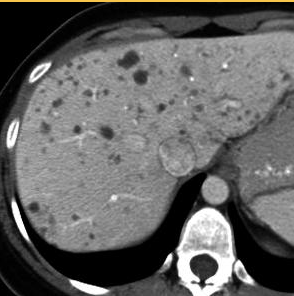

DDx for patchy areas of low attenuation within the liver, post IV contrast?

1: Cirrhosis 2: Hepatitis 3: Portal Vein Thrombosis 4: Chr. Budd-Chiari 5: Lymphoma 6: Sarcoidosis

How can cirrhotic regenerative nodules be differentiated from malignant neoplastic lesions on CT

Regenerative nodules have the same imaging characteristics as normal hepatic parenchyma but stand out because of their surrounding fibrous bands They measure 3 to 10 mm in size. CT: most regenerative nodules are isointense to the surrounding liver parenchyma and are usually not detected. Occasionally they will appear hyperintense due to iron deposition (siderotic nodules).